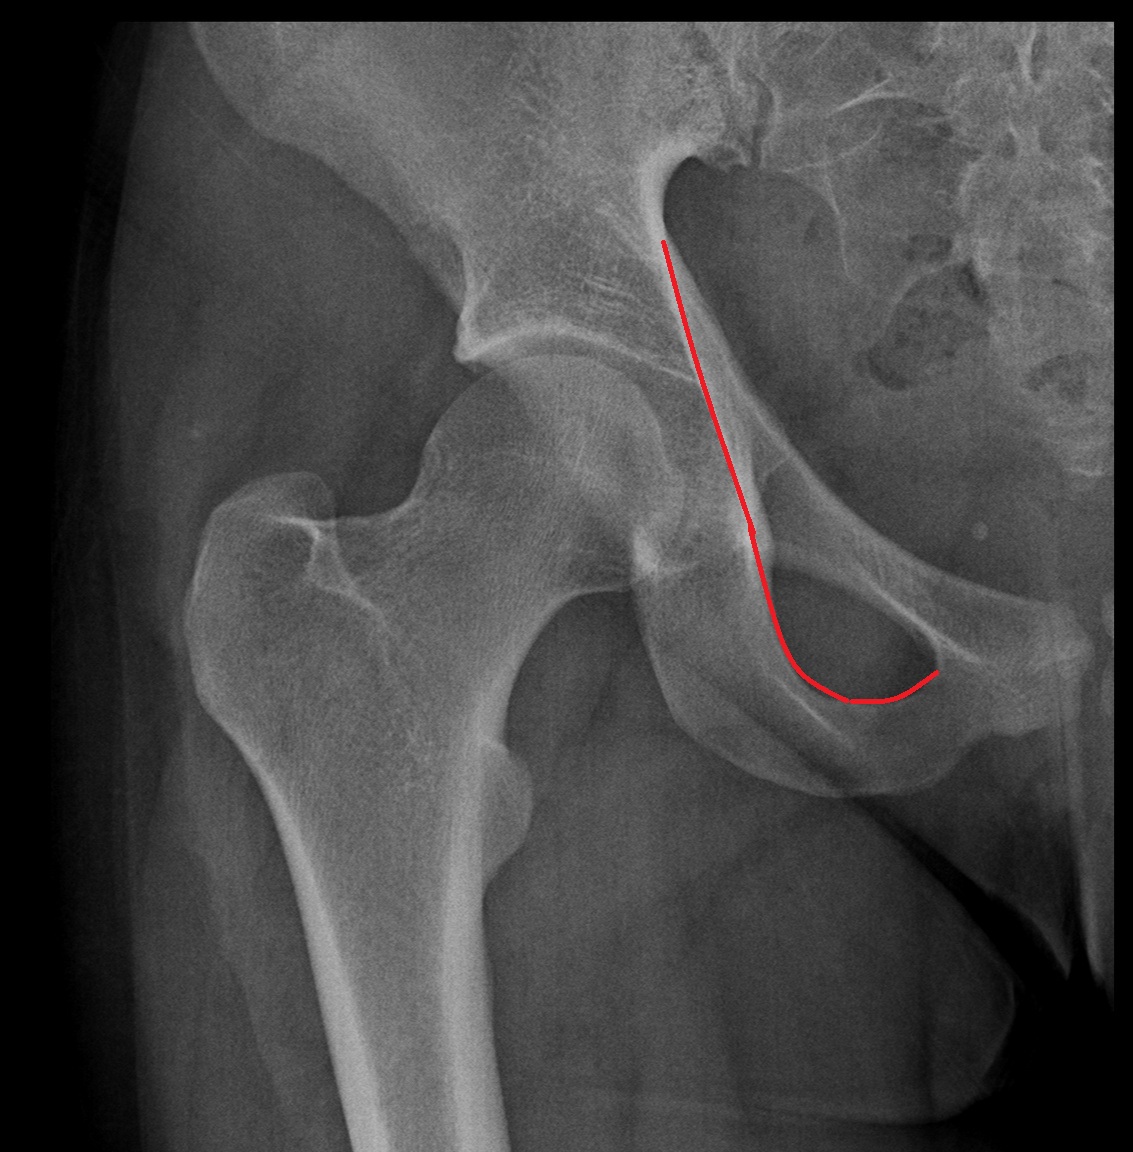

- Acetabular margin (Acetabular rim)

- Acetabulum

- Head of femur

- Neck of femur

- Acetabular labrum

- Hip joint